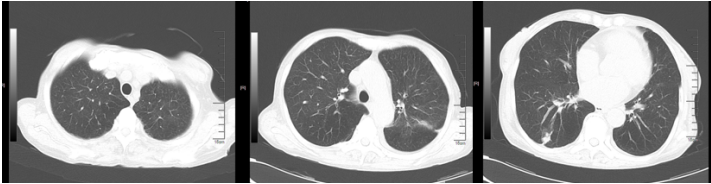

新冠病区诊治过程:鼻导管吸氧;阿兹夫定5 mg qd抗病毒、莫西沙星0.4 g qd抗感染,丙球10 g qd,地塞米松6 mg×2 d,之后予甲泼尼龙40 mg bid抗炎,低分子肝素钠5000单位ih q12h抗凝等治疗。2023年1月10日胸闷气急症状加重。血气分析(FiO2 41.0%):pH 7.39,PaO2 35.6 mmHg,PaCO2 34 mmHg,氧合指数87 mmHg。胸部CT(2023年1月10日,我院):双肺斑片影,符合病毒性肺炎,且较2023年1月6日明显加重(图1);双肾萎缩;双肾结石。

图1  患者胸部CT